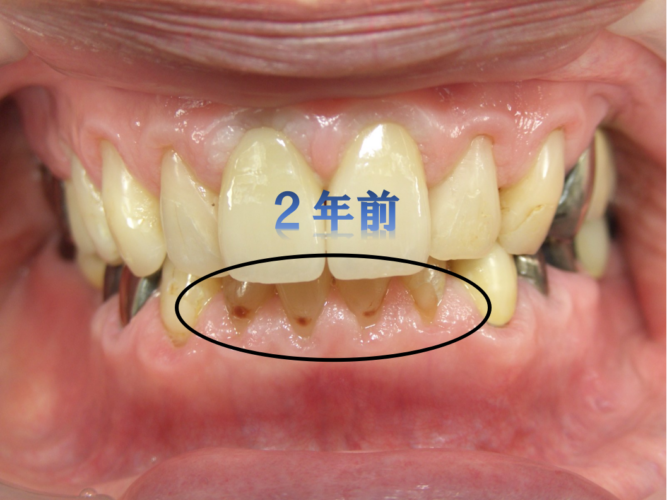

2年ぶりにメンテナンスでお会いしました。

飴が好きで、薬草飴を一日に何個も食べていたそうです。

下の歯の歯ぐきの際が黒くなって、えぐれています。

残念ながら治療が必要な状態の「虫歯」です。

2年前の状態と比べて、明らかに虫歯が進行したのが分かります。